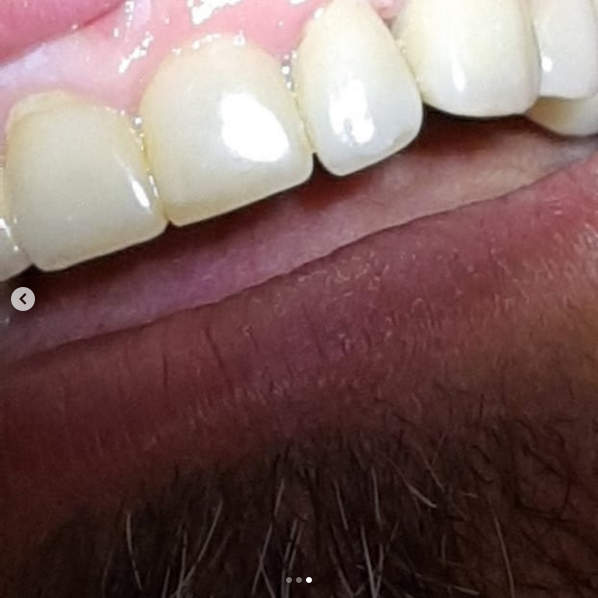

Установка керамической коронки

Пациентка 28 лет обратилась с переломом коронки центрального резца. Проведено удаление с одномоментной имплантацией в лунку дентальным имплантатом «Nobel Biocare» и изготовлением временной коронки. Через 3 месяца проведено протезирование всех 4-х резцов для достижения идеального эстетического результата безметалловыми одиночными коронками.